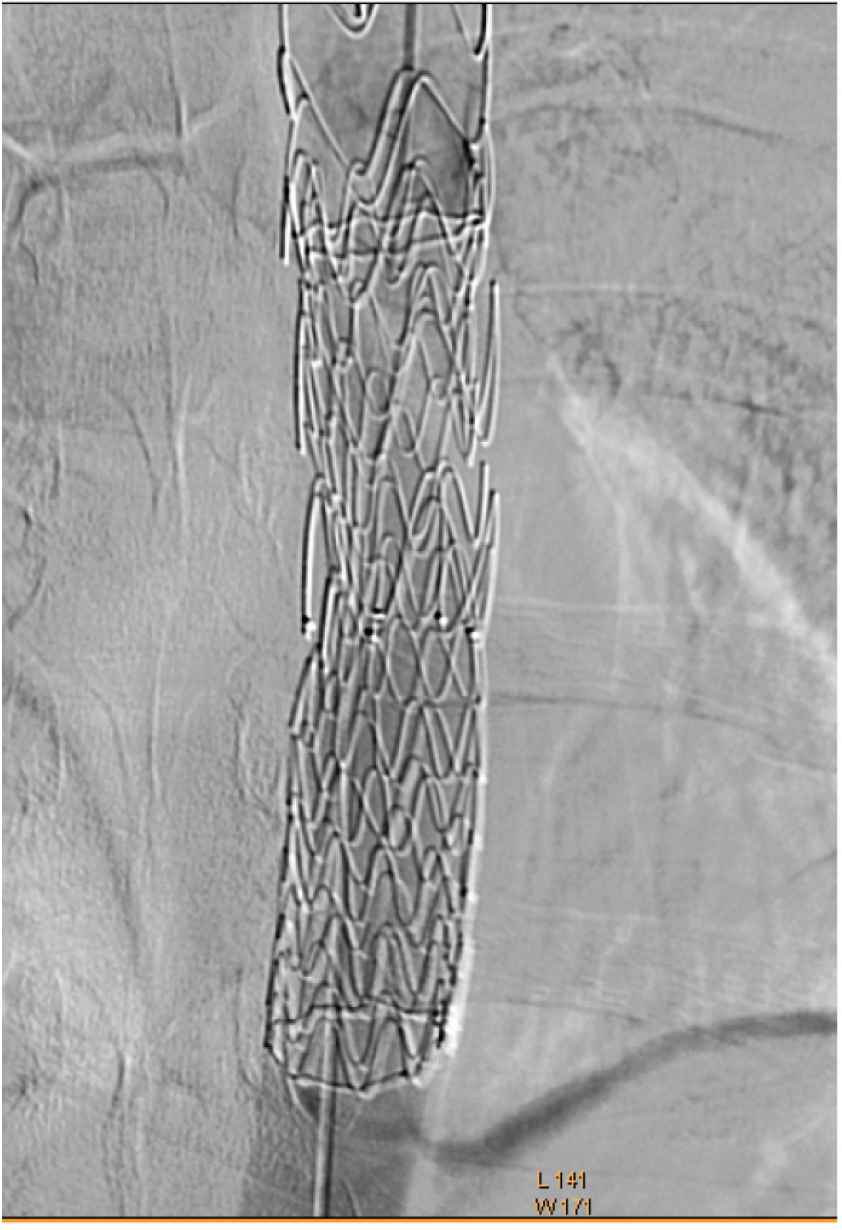

Next, the patient underwent conventional angiography, under local anesthesia and sedation, through 6F right radial access sheath, which confirmed the diagnosis and the true lumen of the aorta (Figure 3).

Conventional angiography showing impaired flow at the collapsed distal previous aortic stent graft.

Intervention with right femoral (20 F) accesses sheath, the Gore Covered (Gore & Associates, Flagstaff, AZ, USA) Gore coered stent was successfully deployed with 4 cm overlap with the old stent. Post-deployment dilatation, using a trilobal balloon, was used (Figure 4), and the normal blood flow in the aorta was achieved (Figure 5). Then, the femoral access site was closed using a closure device.

Conventional angiography showing (A) new stent deployment with overlap of the old fractured stent, (B, C) post-deployment dilatation using trilobal baloon.